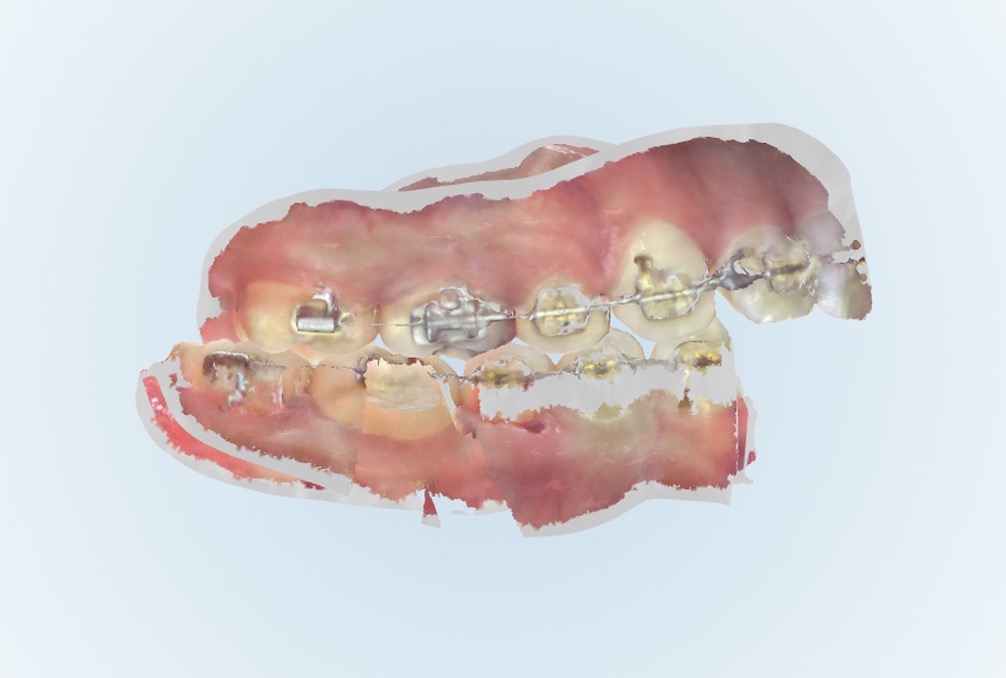

かぶせ物ではなく、ダイレクトボンディングでの治療、また埋入されているインプラント体に問題はなかったため、仮歯のやりかえと上部構造物の製作を行いました。